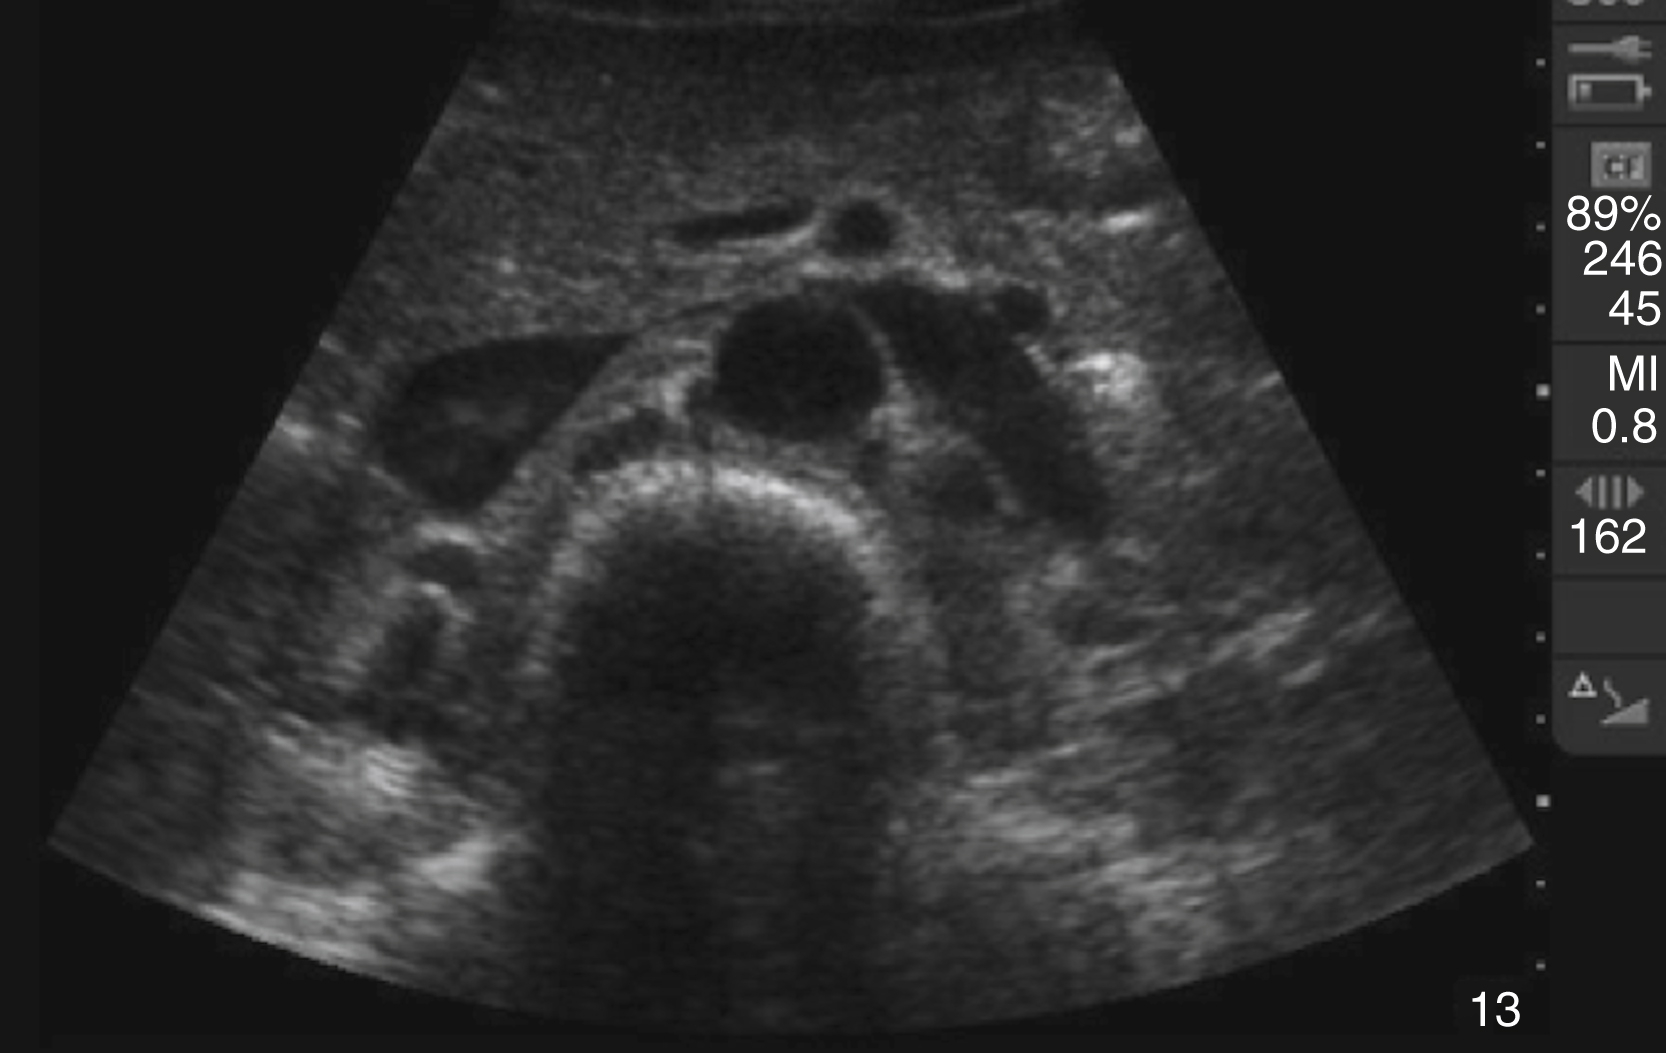

Pathology

Hydronephrosis is characterized by dilation and anechoic fluid accumulation within the renal pelvis and calyces, ranging from mild to severe ( Fig. e3.6 ). Renal and/or ureteral calculi may be identified as echogenic foci with associated shadowing and are usually located within the kidney (nonobstructive) or in the renal pelvis, proximal ureter, or uretero-vesicular junction. Color Doppler placed over the kidney can help differentiate mild hydronephrosis from the renal vasculature, as well as possibly accentuate any renal stones by producing the renal twinkle artifact.

Hydronephrosis with dilation of the calyces and renal pelvis of the kidney showing thinning of the cortex, signifying severe hydronephrosis.